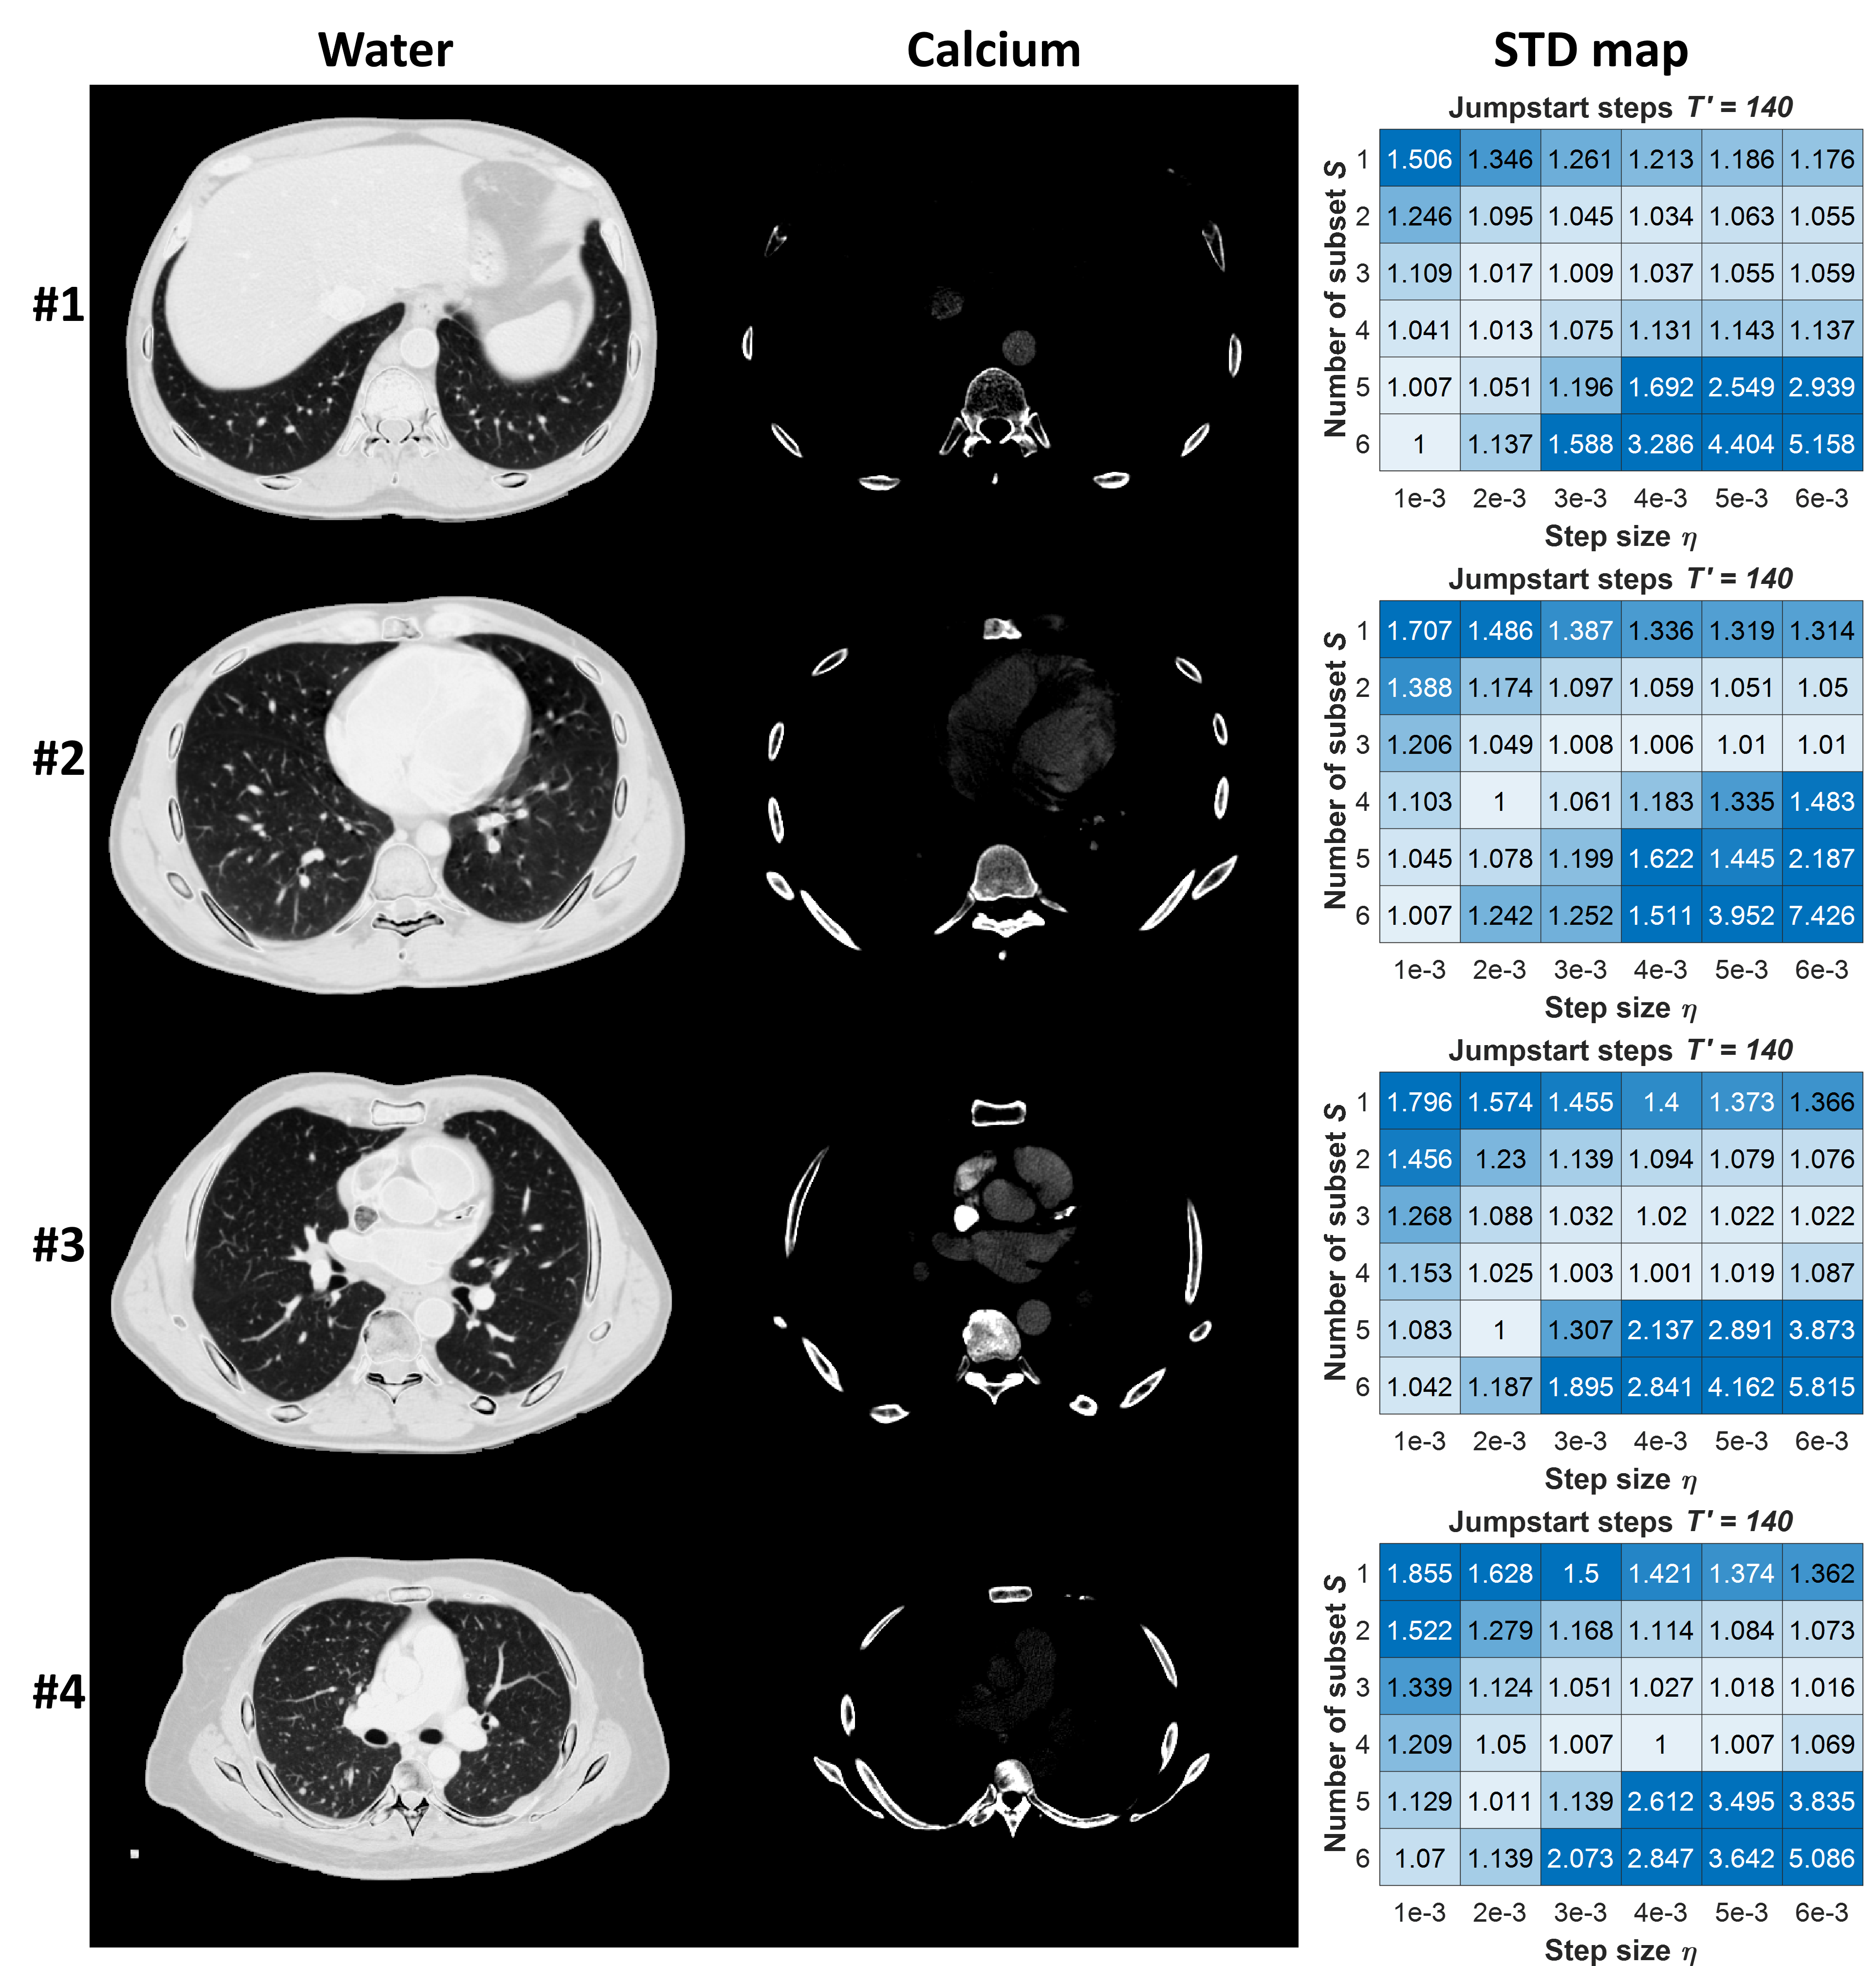

Refer to caption

Figure 8: Normalized STD map (right) for four slices (left) at different locations. Display window: water: [0,1.2]g/ml01.2𝑔𝑚𝑙[0,1.2]g/ml, calcium: [0,0.2]g/ml00.2𝑔𝑚𝑙[0,0.2]g/ml

In this section, we present the results of the parameter sweep for the dual-layer CT system.

The parameter sweep was performed for Tsuperscript𝑇T^{\prime}, η𝜂\eta, and S𝑆S, and the corresponding normalized STD heatmaps are displayed in Fig.6. The subplots for each time step exhibit the similar trends. There is a low-variability region extending from top right to bottom left. For T120superscript𝑇120T^{\prime}\geq 120, the difference in the minimal STD for optimal η,S𝜂𝑆\eta,S is smaller than <1%absentpercent1<1\%.

To investigate how the parameter η,S𝜂𝑆\eta,S selection affects the decomposition results, we display the decomposition and corresponding STD map of 5 different parameter settings with T=140superscript𝑇140T^{\prime}=140 in Fig.7. For small S,η𝑆𝜂S,\eta (e.g. S=1,η=0.001formulae-sequence𝑆1𝜂0.001S=1,\eta=0.001), the STD map shows large variability particularly around the edges, as well as features that, while realistic, are inconsistent with the ground truth. Increasing S,η𝑆𝜂S,\eta within a certain range led to significant STD reduction. However, when the optimal point was exceeded, i.e., S=3,η=0.003formulae-sequence𝑆3𝜂0.003S=3,\eta=0.003 in Fig.7, the STD increases again. Unlike the high STD caused by variation in fine structures, this increase was due to background signal fluctuations.

In Fig.8, we plot the STD map of slices at different anatomical locations, revealing that the heatmaps of different slices displayed similar trends. This suggests that parameters optimized on one slice or a group of representative slices can be reasonably applied to other slices, thereby eliminating the need for an anatomical-specific parameter tuning (at least for these thoracic CT). This consistency across slices underscores the robustness and generalizability of the parameter optimization process, streamlining the application of spectral DPS.